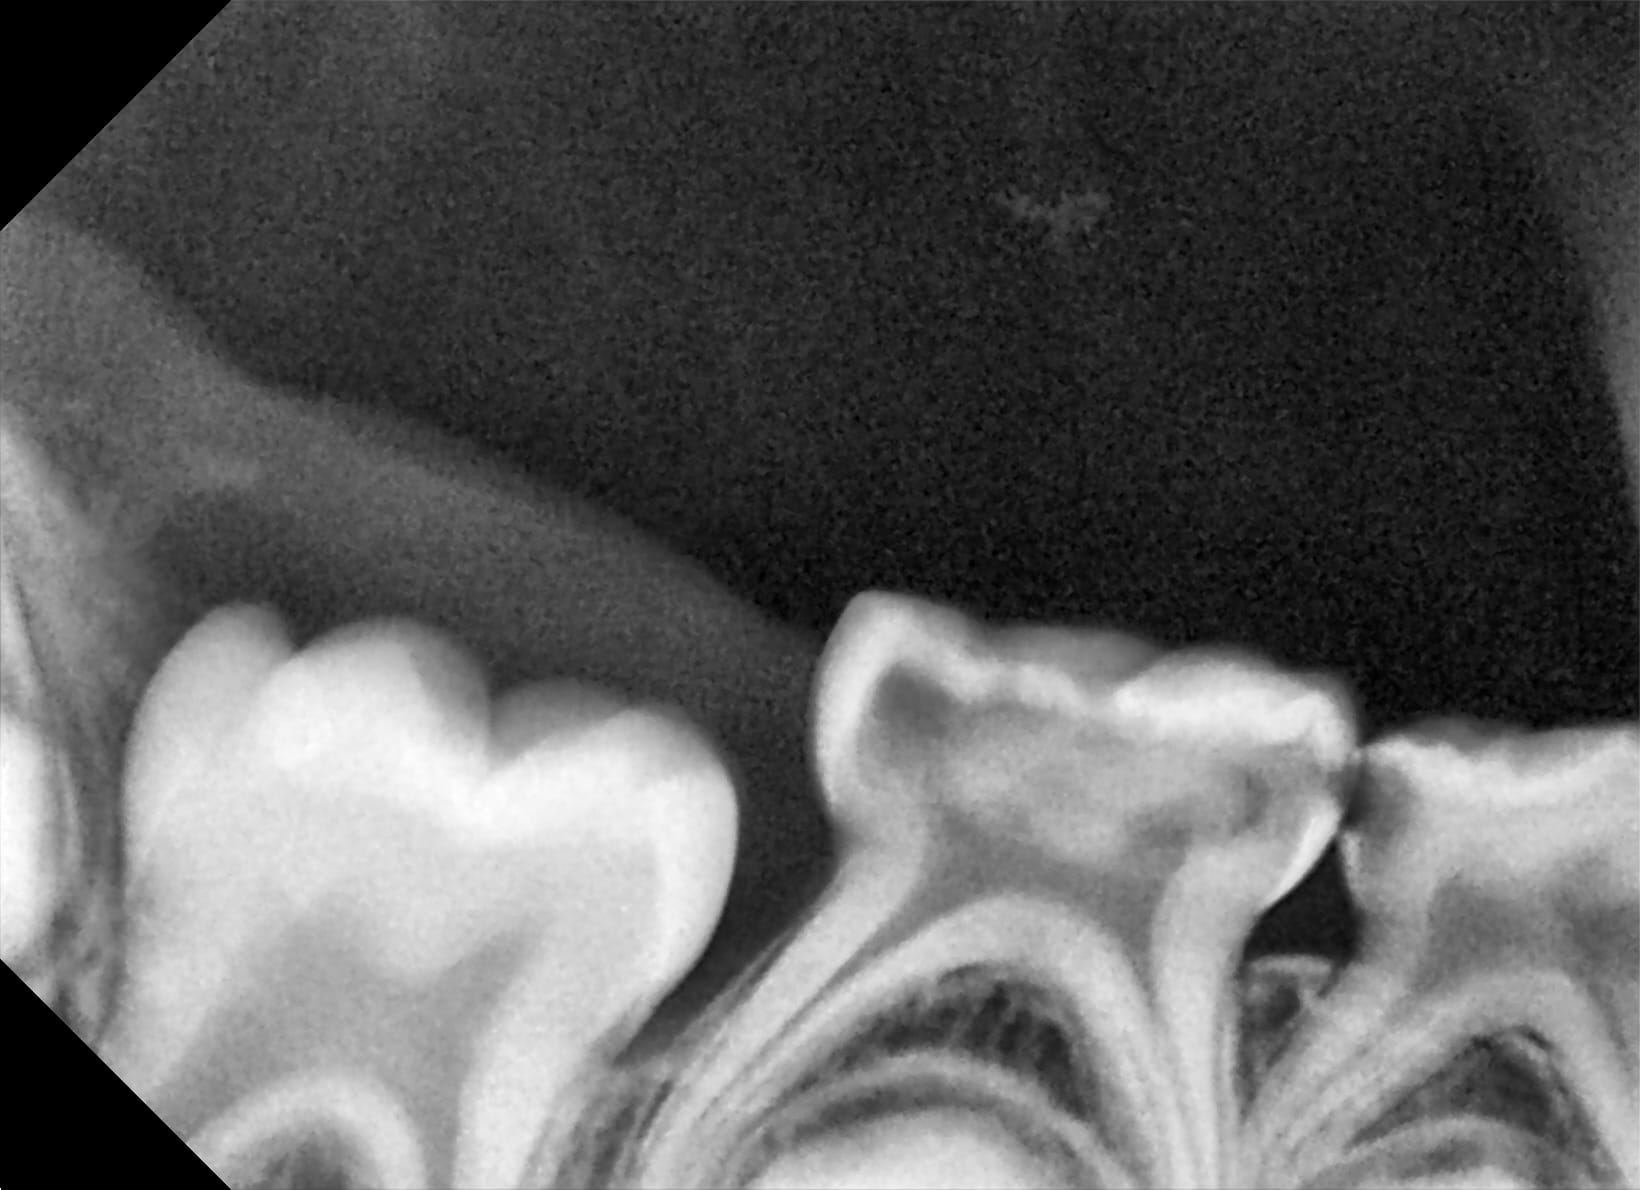

Capture_d_écran_2019-09-04_21.19.10_a55pcs.png